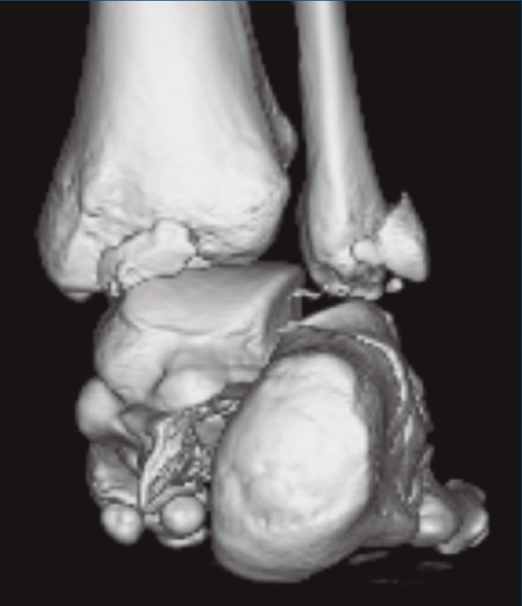

Figura 1. Luxación del astrágalo en mortaja tibioperonea, fractura maléolo peroneo y espacio subperoneo ocupado por calcáneo.

Figura 2. Fractura maléolo peroneo y tibial posterior. Trazo entre fragmento anteromedial y posterolateral.

Figura 3. Desplazamiento entre fragmento anteromedial (sustentaculum tali) y posterolateral (tuberosidad).

Se trata de un varón de 19 años que ingresa en reanimación tras precipitarse desde una altura de aproximadamente 10 metros. El paciente presenta una fractura estallido de L3 con afectación del canal medular junto con una fractura del vértice inferior de L4, así como una fractura luxación de calcáneo, asociada a una fractura del maléolo peroneo y del maléolo tibial posterior (Figuras 1 a 6) diagnosticadas mediante TC total body (por eso no se dispone de radiografías simples al momento del ingreso). Como podemos comprobar, se trata de una fractura de doble trazo de tipo hundimiento/depresión de la carilla articular (Figuras 5 y 6).

Figura 4. Luxación fragmento posterolateral.

Figura 5. Fractura maléolo peroneo, luxación astrágalo, fractura de doble trazo en calcáneo.

Figura 6. Fractura de doble trazo; se evidencia afectación de la articulación calcaneocuboidea.